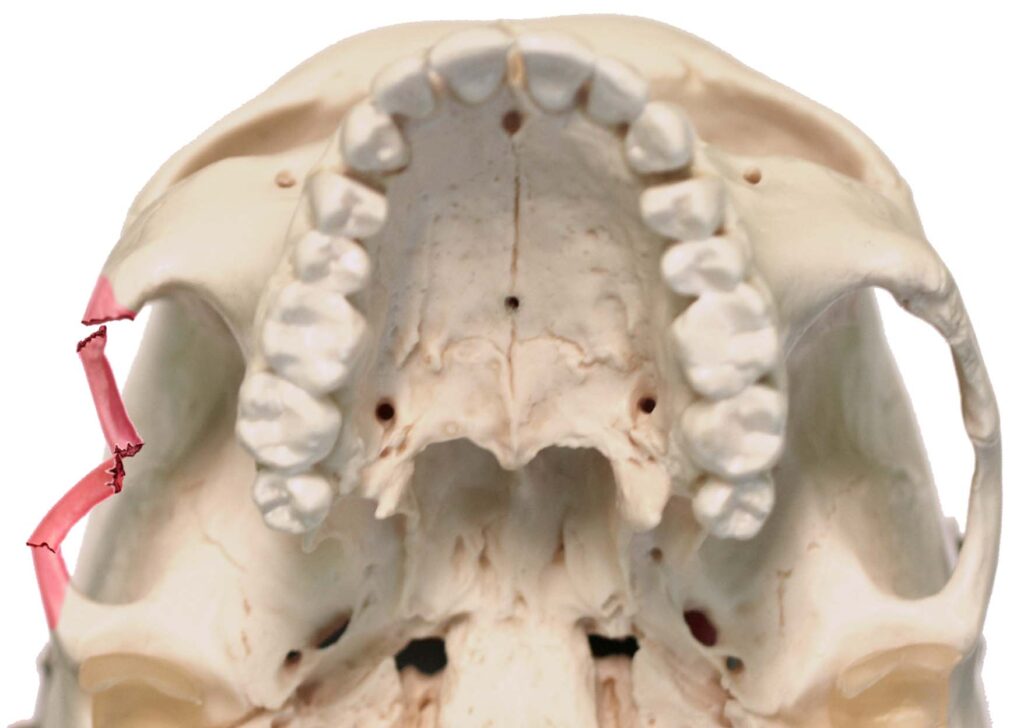

برای یک جراح فک و صورت، تشخیص نوع» شکستگی حیاتی‌ترین بخش کار است. ما معمولا شکستگی‌های ماگزیلا را بر اساس طبقه‌بندی مشهور «لوفورت» Le Fort دسته‌بندی می‌کنیم که نشان می‌دهد خط شکستگی دقیقا از کجا عبور کرده است:

شکستگی لوفورت

تشخیص دقیق نوع شکستگی لو فورت فقط با سی‌تی اسکن سه‌بعدی امکان‌پذیر است و طرح جراحی بر اساس آن ریخته می‌شود. برای دریافت اطلاعات بیشتر در مورد انواع شکستگی لوفورت و جراحی ارتوگناتیک به این صفحه مراجعه کنید.